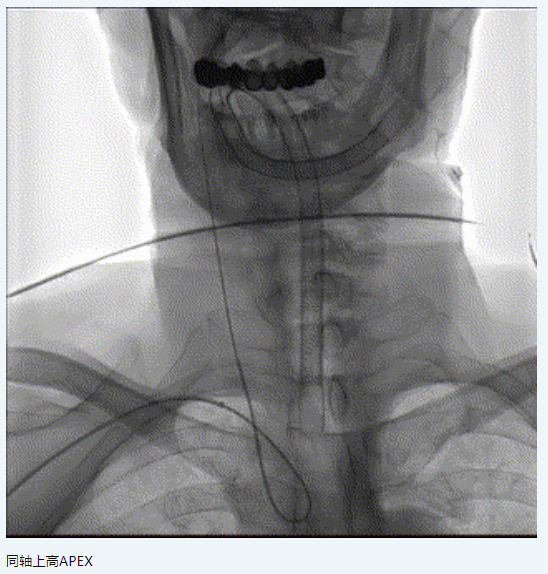

橈動脈系統(tǒng):APEX TRA SYSTEM 7F-105cm+140cm-SIM2

6.7F APEX TRA SYSTEM橈系統(tǒng):1、外徑細(2.32mm),對橈動脈侵擾小,內(nèi)腔大(0.081”):可兼容5F中間導管高到位;經(jīng)橈專用,弓部支撐性較長鞘、導引導管、中間導管、DA更強;APEX橈系統(tǒng)配套有130/140cm長SIM2,長SIM2管同軸治療可避免交換失敗,使顱內(nèi)病變更加便捷。